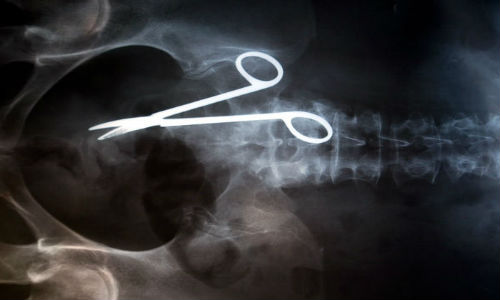

மருத்துவ உலகம் கண்டு வியந்த எக்ஸ் ரே படங்கள்

வயிற்றில் கத்திரிகோல் உள்ளது.